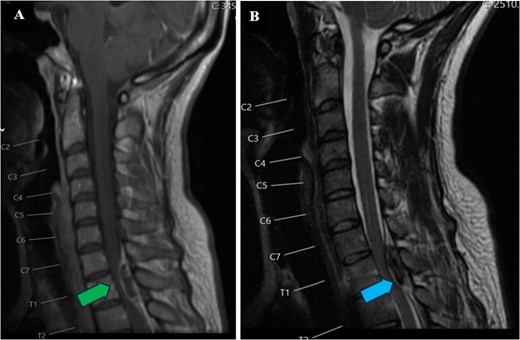

A 34-year-old female with no significant medical history and no regular medications presented to the emergency room with sudden onset of lower cervical to upper thoracic back pain radiating to the left shoulder. The symptoms rapidly progressed, leading to the loss of independent walking despite no prior trauma. Within hours, spastic paraplegia with sensory loss below the T1 level bilaterally developed. Initial blood tests were normal, including a complete blood count and coagulation profile. Total neuroaxis CT and thoracic spine CTA revealed a mass occupying the posterior aspect of the spinal canal between C7 and T2. Subsequent magnetic resonance imaging (MRI) indicated findings consistent with an acute spinal subdural hematoma causing cord compression, most pronounced at the C7-T2 level, without any changes in cord signal as shown in Fig. 1.

Preoperative MRI of the cervical spine. T1 (A) and T2 (B) sagittal views. Lesion is hyperintense (green arrow) on T1-weighted image and hypointense to isointense (blue arrow) on T2-weighted image at C7-T2 level.